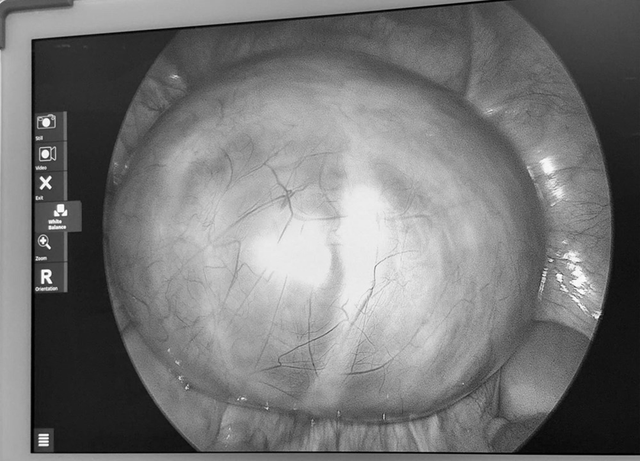

Tưởng đau bụng thông thường, tá hỏa khi phát hiện khối u... 14cm. Ảnh minh họa.

Tại viện qua siêu âm, các bác sĩ phát hiện buồng trứng trái có khối u lớn khoảng 14cm, cấu trúc nhiều vách. Sau hội chẩn, ê-kíp khoa Phụ sản đã tiến hành phẫu thuật vào ngày 3/4. Ca mổ diễn ra thuận lợi, khối u được bóc tách hoàn toàn, đồng thời bảo tồn tối đa chức năng sinh sản cho người bệnh.